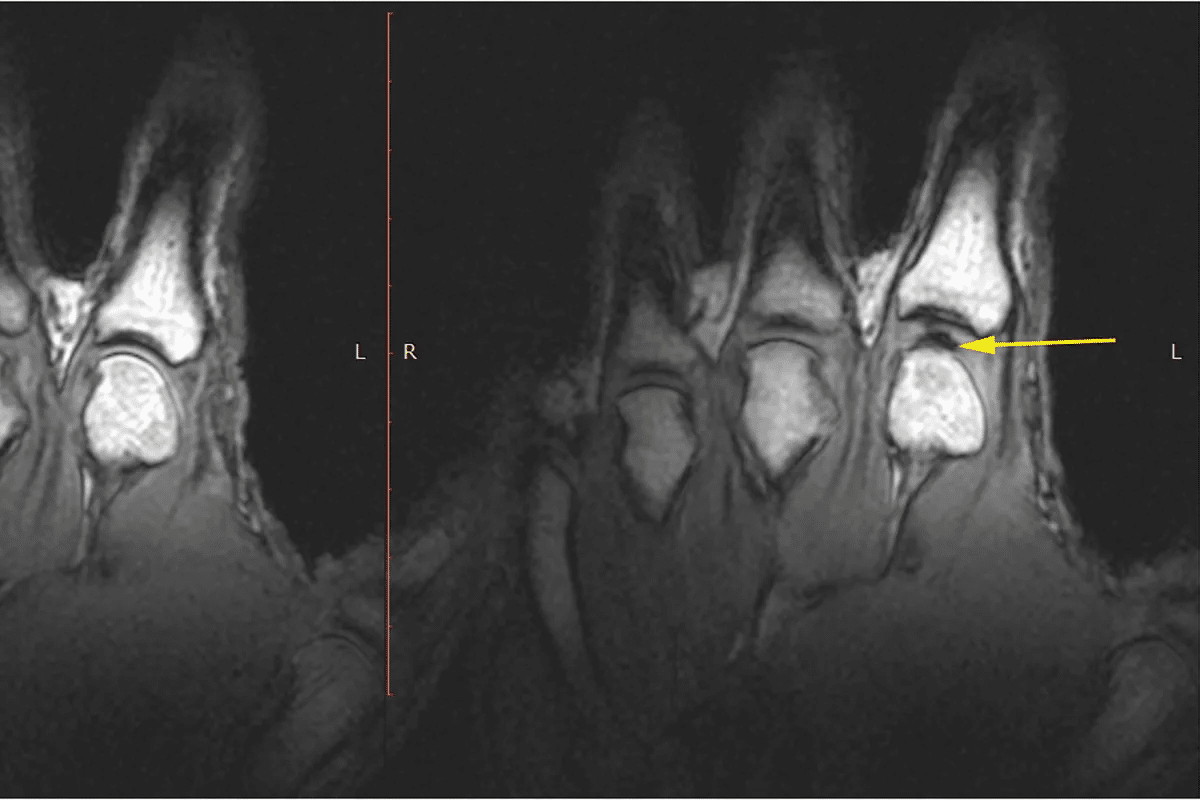

Rheumatoid Arthritis Detection

Rheumatoid arthritis (RA) mainly affects the joints and is chronic. MRI is great for checking RA, spotting synovitis, tenosynovitis, and bone marrow edema. These signs are important for diagnosing RA.

Studies show MRI catches these signs in 39% of early arthritis and 68% of RA cases. This makes MRI very good at finding RA.